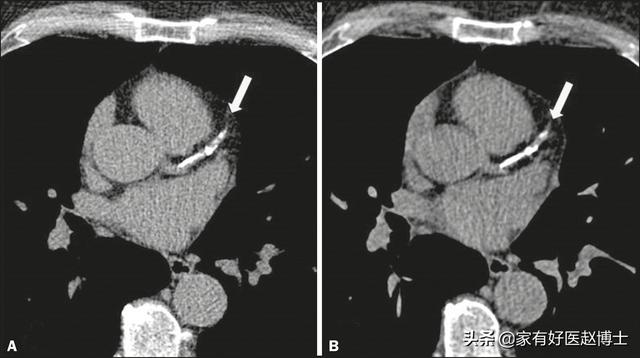

第四个要说的是“动脉钙化”,动脉钙化在人群当中也很常见。很多时候是在体检报告的胸部X光片或CT扫描结果里,可以看到“主动脉钙化”、“冠脉钙化”等提示。

钙化的本质是钙质在血管壁内的沉积,这被认为是动脉硬化的明确信号,同时也是血管老化的表现。